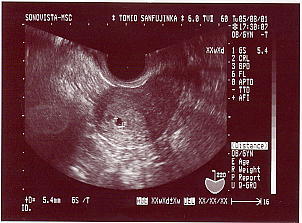

12週目のエコー 赤ちゃんは正面を向いてます。 手足がピョコピョコ動いてるのが わかりました。 やっとこさ45ミリです。 とりあえず宇宙人みたいだけど、 なんとか人間っぽくなってきました。 |